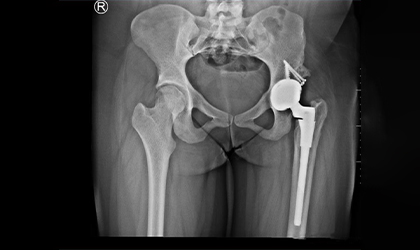

26-year-old woman diagnosed with hip dysplasia characterized by a shallow hip socket. She underwent a left total hip replacement using a specialized prosthesis known as the S-ROM system. Additionally, bone grafting was performed to reconstruct and reinforce the socket walls for better implant support.This is one of the youngest girls I have done a hip replacement in. Did her right hip when she was 13 and the left a year later. She is a blood cancer survivor. She had collapse of both her hips related to chemotherapy (which actually saved her life). She had ceramic bearings. Presently totally symptom free pursuing her higher studies.